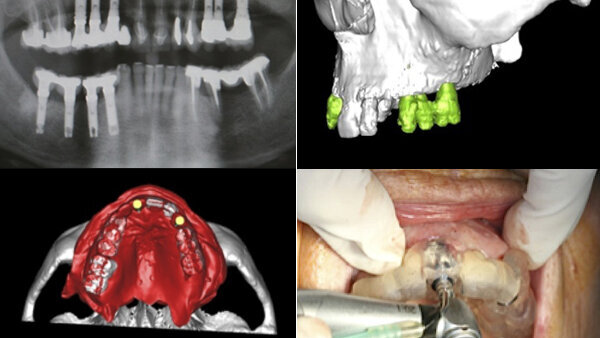

La cirugía implantológica guiada por ordenador se puede definir como la realización precisa de un plan de tratamiento en base a un estudio de TAC que proporciona un conocimiento exhaustivo de la anatomía del paciente y que permite, mediante la fabricación de dispositivos de guiado personalizados, la transferencia precisa de la planificación a la boca del paciente, habilitando protocolos de cirugía mínimamente invasiva y prótesis prequirúrgica inmediata.

El uso de tecnologías que generan modelos anatómicos en tres dimensiones a partir de una tomografía computarizada de cada paciente permite al cirujano oral o maxilofacial y al odontólogo rehabilitador determinar digitalmente la posición, longitud y diámetro ideal de los implantes respecto a la futura rehabilitación protésica ideal para cada caso. A partir de esta planificación virtual, se crea un modelo médico estereolitográfico (resina acrílica fotopolimerizable mediante láser) del maxilar y/o mandíbula del paciente, y se fabrica una férula quirúrgica estereolitográfica que permite colocar los implantes en boca en la posición planificada en la computadora.

Las guías quirúrgicas estereolitográficas contienen cilindros metálicos orientados en la misma trayectoria que los implantes planificados virtualmente. A través de estos tubos y con la férula quirúrgica posicionada en la boca del paciente, se realiza la secuencia de fresado y la colocación del implante, transfiriendo de esta manera la planificación del ordenador a la boca del paciente1.

Por lo tanto, la cirugía implantológica oral mínimamente invasiva, transgingival o sin colgajo, puede ser un candidato ideal para la cirugía guiada por ordenador, aprovechando las ventajas que ofrecen la tomografía computerizada, los modelos anatómicos 3D e impulsada por la planificación por ordenador en base a la prótesis implantosoportada final y a la posibilidad de fabricar férulas quirúrgicas estereolitográficas para la colocación de los implantes, evitando daños estructurales y anatómicos o complicaciones postoperatorias14.